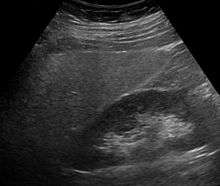

Ultrasound showing diffuse increased echogenicity of the liver.

Imaging studies are often obtained during the evaluation process. Ultrasonography reveals a "bright" liver with increased echogenicity. Medical imaging can aid in diagnosis of fatty liver; fatty livers have lower density than spleens on computed tomography (CT), and fat appears bright in T1-weighted magnetic resonance images (MRIs). No medical imagery, however, is able to distinguish simple steatosis from advanced NASH. Histological diagnosis by liver biopsy is sought when assessment of severity is indicated.